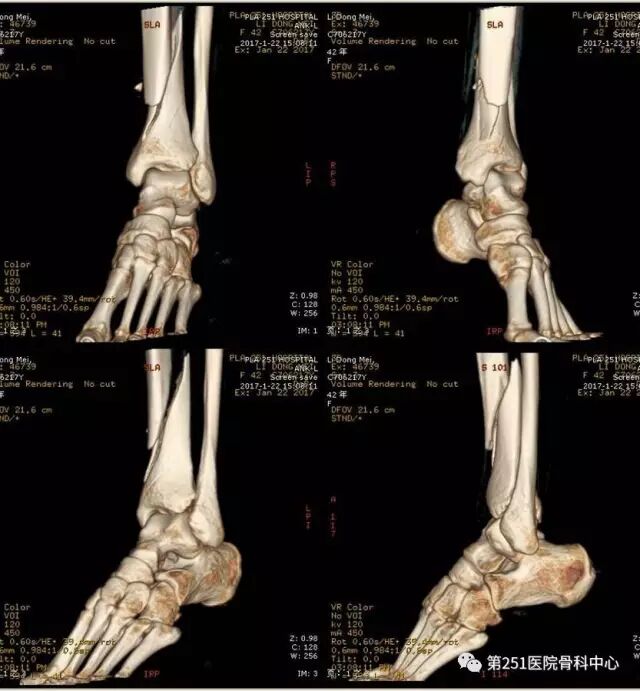

病例7:女性,43岁,车祸伤,胫腓骨远端骨折。